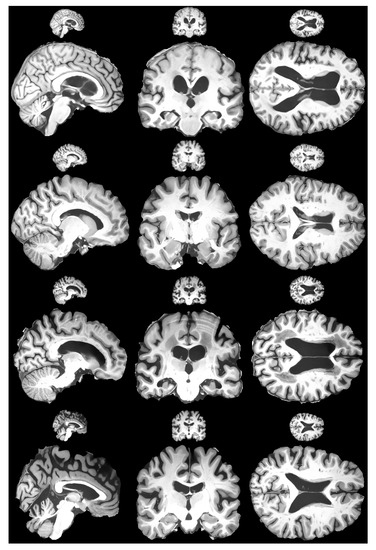

4.1. Experimentation Data

4.3. Results